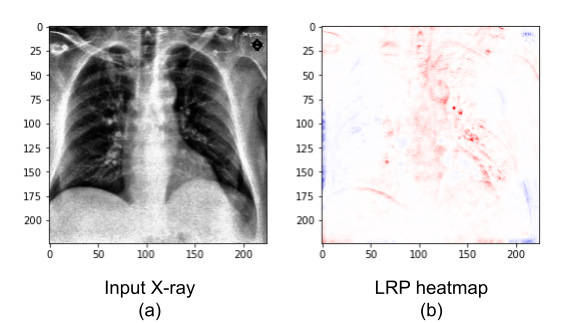

Figure 7: The X-ray (a) is an image from our external test dataset (unlike Figure 6, which presented training X-rays), correctly classified as Covid-19. It presents a male patient in the first day of Covid-19 symptoms. The mask (b) and the heatmap (c) were created with the stacked DNN. Red colors indicate areas that the DNN associated to Covid-19, while blue areas were associated to the classes pneumonia or normal

We can further understand the differences between the two DNNs (with and without segmentation) when we analyze them using Layer-wise Relevance Propagation. Therefore, we show, in Figure 8, a LRP analysis for the same X-ray in Figure 7, but created using the DenseNet201 (without segmentation) instead of the stacked DNN. We note that this DNN correctly classifies the image, but it assigned a much lower Covid-19 probability, of 46.2%. Red areas in the map were associated with the Covid-19 class, while blue areas were associated with the other classes.

Refer to caption

Figure 8: Covid-19 X-ray (a) and heatmap (b). Unlike Figures 6 and 7, this heatmap was created with the DNN without lung segmentation. The X-ray is an image from our external test dataset, correctly classified by the network. It presents a male patient in the first day of Covid-19 symptoms. Red colors indicate areas that the DNN associated to the Covid-19 class, while blue areas were associated to pneumonia or normal

We observe, in Figure 8, that there is relevance outside of the lungs. Its existence may explain why the stacked DNN has better generalization (4.7% higher accuracy on the external test dataset) than the network without segmentation. The relevance outside of the important areas might indicate dataset biases learned by the DNN. However, some Covid-19 signs, indicated in the heatmap in Figure 7 can still be seen on Figure 8 (mostly on the left lung).